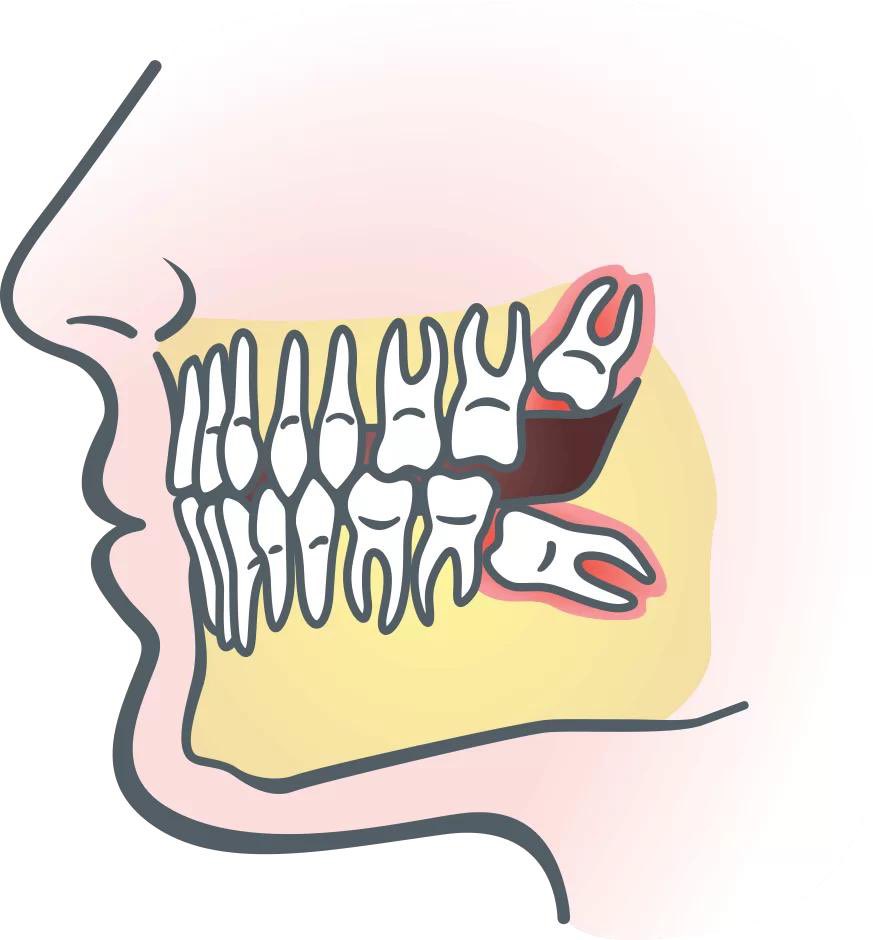

إما ان تظل مدفونة فى عظام الفك كلية ، أو تحاول البزوغ جزئياَ، أى يظهر جزء منها بالفم والباقى مدفوناَ بعظام الفك .

وأبرز أسباب عدم ظهور ضرس العقل هى :

- إختفاء البرعم الخاص به منذ البداية .

- صغر حجم الفك بحيث لايسمح لنمو أو ظهور ضرس العقل.

- قد ينمو ضرس العقل بصورة عرضية أو مائلة لاتسمح له بالظهور بالفك .